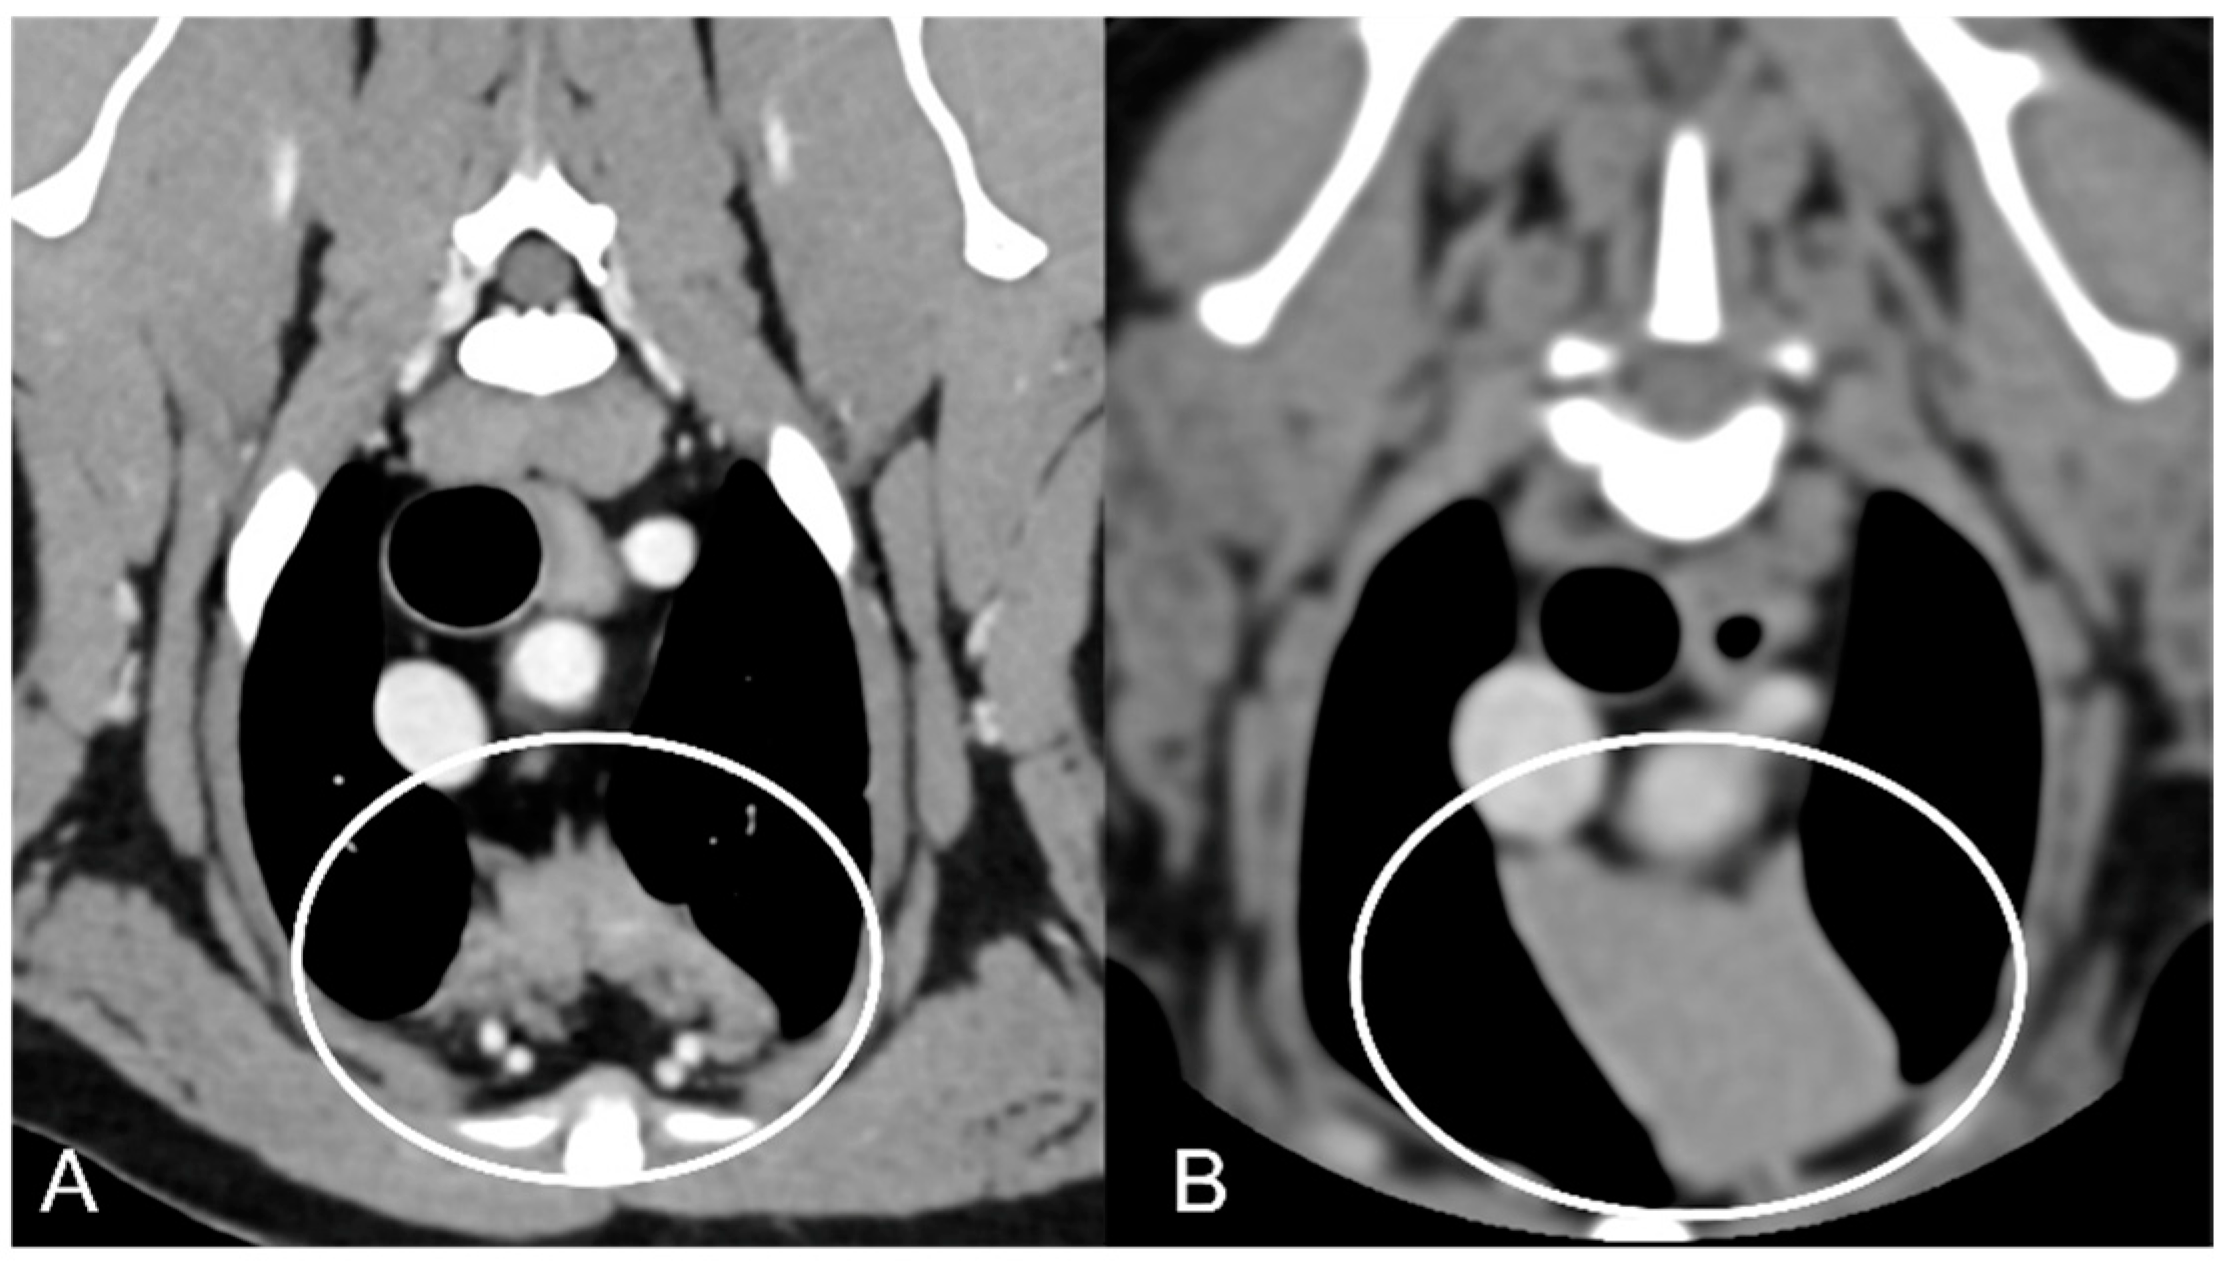

The overall appearance was lobulated in all of the adult dogs and homogeneous in all of the juvenile dogs (Figure 1 and Figure 3). The thymus was left-sided in all of the adult dogs, while it was located in the midline in a few juvenile dogs; one presented a thymus on the right side due to situs inversus (Figure 4). The maximum dimension of the thymus in the adult dogs group was always the length, while in some juvenile dogs, the maximum diameter was the width (Figure 2). The dimensions of the thymus were variable between different patients, with several breeds included and large differences in body weight between the dogs. For this reason, a ratio between the maximum diameter of the thymus (measured in cm) and the body weight (measured in kg) was calculated for each dog. The median ratio in the adult dogs group was 0.2 (minimum: 0.06; maximum: 0.4), while in juvenile dogs, it was 0.4 (minimum: 0.1; maximum: 1.4). The dogs with the higher ratio (>1) were in the juvenile group and they presented with spinal a cyst and enteritis and were 6 and 7 months old, respectively. The dogs with the lower ratio (<0.1) were in the adult group and they presented with muscular hemangiosarcoma (one dog) and synovial cell sarcoma (two dogs) and were 2, 6, and 8 years old, respectively.

The thymus was less attenuating in adult dogs compared to young dogs, with a median of the mean pre- and post-contrast attenuation values lower in adult dogs compared to juvenile dogs (Table 1). In 5/11 (45%) adult dogs, the minimum pre-contrast attenuation values were negative values (from −22 to −2 HU), due to the presence of multiple, hypoattenuating, thick septi within the thymic parenchyma (Figure 5).

Figure 3. Appearance of the parenchyma of the thymus (circled) in an adult dog (A) compared to a young dog (B). Post-contrast transverse CT images. The appearance is lobulated in adult dogs (A) and homogeneous in young dogs (B).